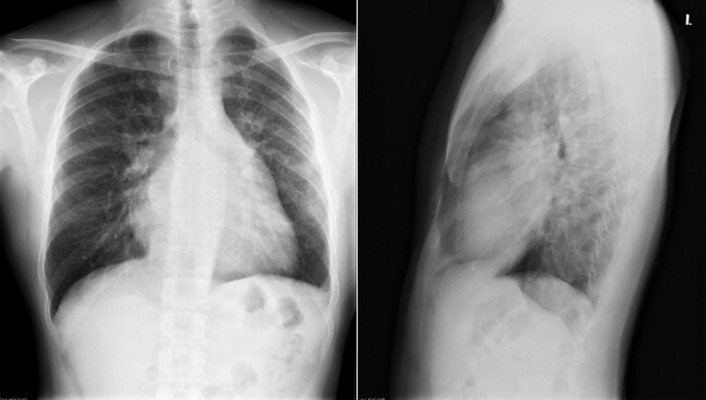

The radiographic findings of mitral stenosis ( Graphic 15-1 ; Figs. 15-1 to 15-16 ) reflect the pressure overload of the left atrium and pulmonary veins, and later of the right heart. As well, the commonly associated chronic atrial fibrillation contributes to (bi)atrial dilation. Associated rheumatic valvular lesions such as mitral regurgitation, tricuspid regurgitation, aortic insufficiency, and aortic stenosis/aortic insufficiency are common, and they alter the appearance of the heart.